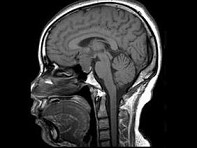

女,38岁,左侧视力下降伴头昏1个月余,根据所提供图像,最可能的诊断是()

女,38岁,左侧视力下降伴头昏1个月余,根据所提供图像,最可能的诊断是()

[单选题]女,38岁,左侧视力下降伴头昏1个月余,根据所提供图像,最可能的诊断是()A . 颅咽管瘤B . 垂体嫌色细胞腺瘤C . 视神经胶质瘤D . 软骨瘤E . 脑膜瘤